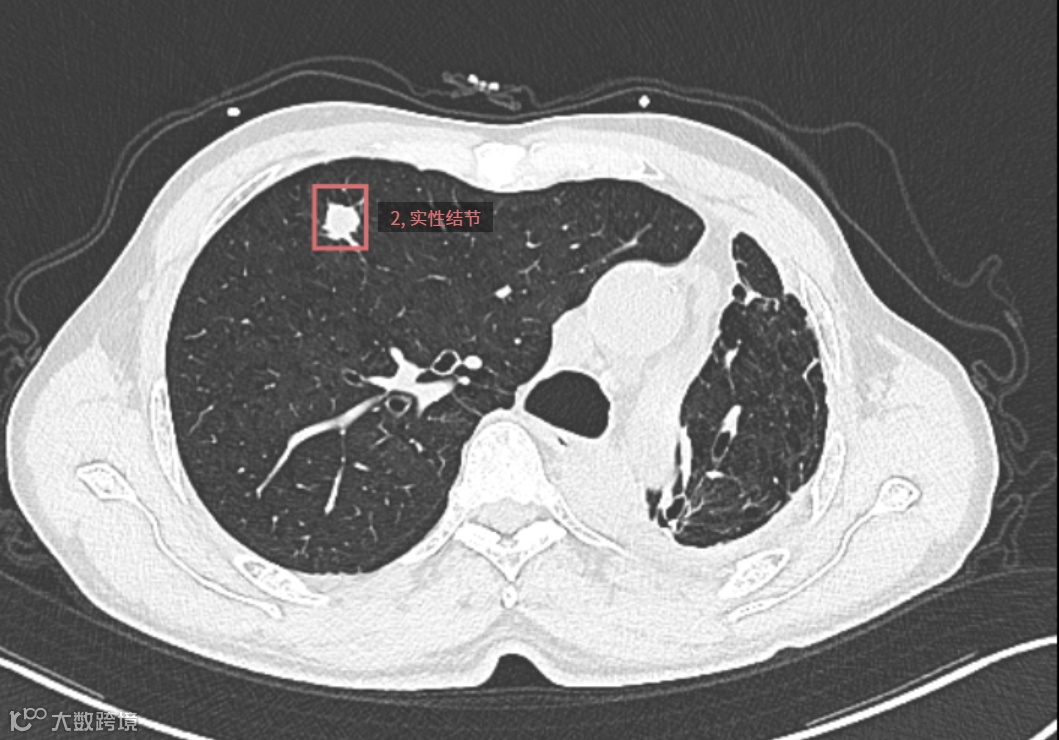

检查所见:患者接受左下肺切除术后,残余肺组织以左肺上叶尖段为主,伴右肺代偿性过度膨胀及形态结构改变。右肺上叶前段可见一实性结节,大小约13.6mm×11.5mm,边界尚清,密度欠均,边缘呈浅分叶状。余右肺散在少许条索影及肺气肿表现。

▲▲▲检测框所指为结节